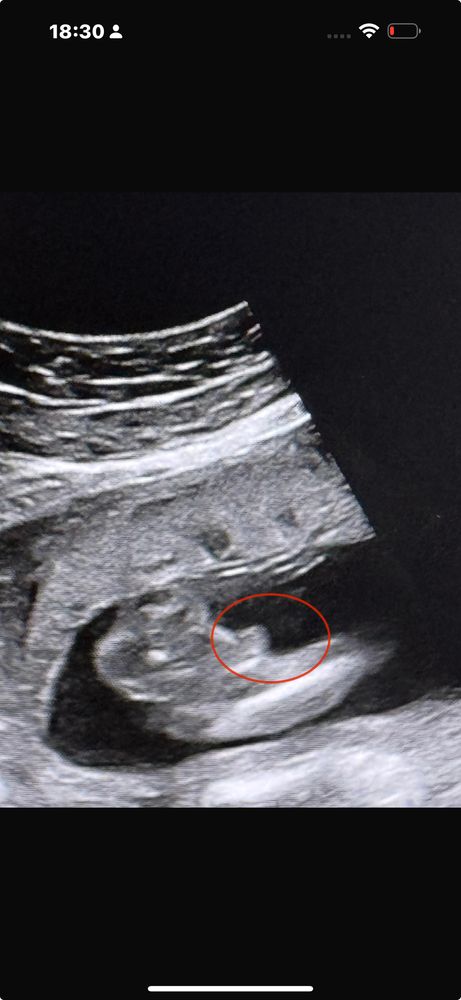

Девочки помогите🥹🙏

По моему на нижнем фото вы ножку обвели 😃 а на первом непонятно. Мне в 13, 16 недель говорили мальчик сто процентов, так и есть. В 19 недель показали четко как выглядит наше отличие) и на 2 скрининге в 21 неделю тоже показали) если узист на таком сроке не может рассмотреть из-за того, что малыш прикрыл, то предполагать бессмысленно, тут вот именно что гадать кому что покажется)

Лимоночка, в 13,16 и вот фото которые приложила в 20 недель предполагали мальчика. Вчера было ровно 26 недель и малыш прикрыл. А я до сих пор на 100% не знаю кто у нас 😄

Могу ошибаться конечно,но мне кажется это мальчик🙈

14 недель. Помогите определить пол =) Пол ребенка